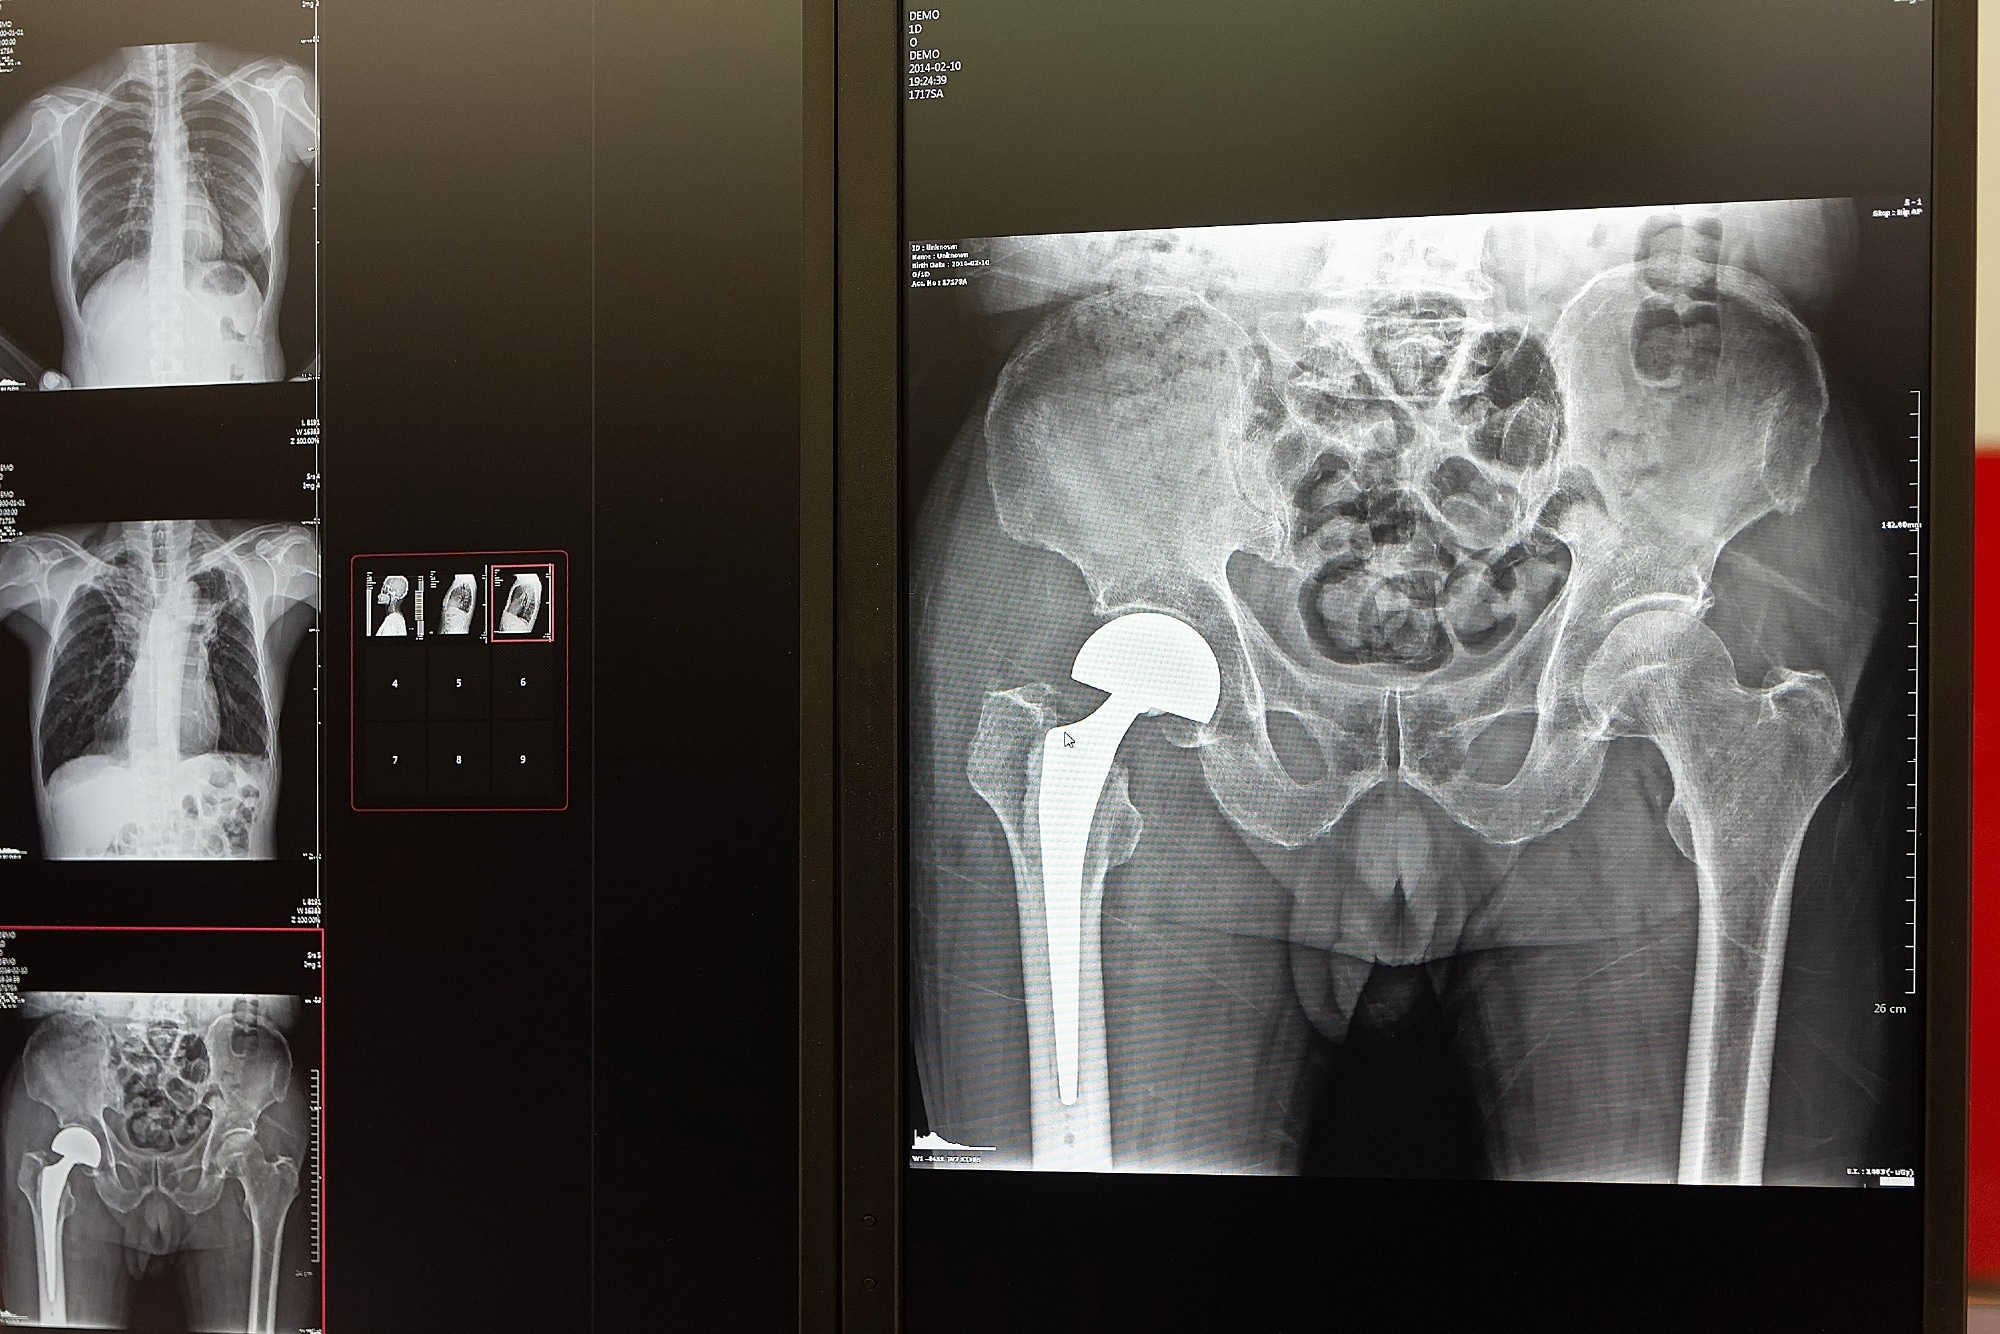

Study: Preoperative Gait Speed as a Predictor of Patient-Reported Outcomes After Total Hip Arthroplasty - Insights from Patient Acceptable Symptom State and K-Means Clustering Analyses. Image Credit: DmyTo / Shutterstock.com

Total hip arthroplasty, commonly known as a hip replacement, is a surgical procedure performed to improve mobility in people with severe hip injuries, many of which are due to osteoarthritis. This surgery is associated with excellent long-term outcomes; however, postoperative recovery and clinical responses vary among individuals.